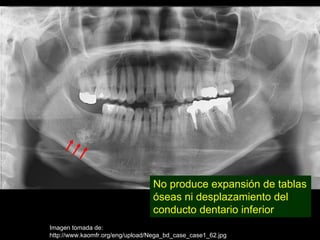

• No produce expansión de tablas óseas ni

desplazamiento del conducto dentario

inferior

No produce expansión de tablas

óseas ni desplazamiento del

conducto dentario inferior

Imagen tomada de:

http://www.kaomfr.org/eng/upload/Nega_bd_case_case1_62.jpg